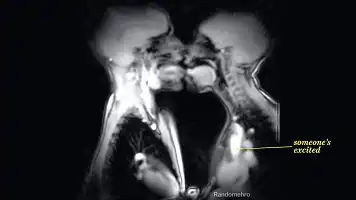

作为全身最薄的皮肤,嘴唇的厚度只有面部皮肤的https://imgs.wenkuwang.org/upload/1/6,且布满了敏感的神经末梢,通过触碰接吻,大脑就会释放出强烈的X激素——“爱情激素”催产素。

传递快乐的神经介质——“快乐源泉”多巴胺,从而引发身体的一系列X冲动。